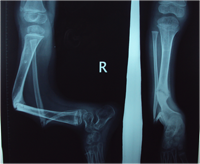

The Monteigga Injury

The Monteigga-fracture dislocation is an injury complex where there is fracture of the ulna and dislocation of the radial head. The ulnar fracture may be incomplete or complete and sometimes there is only plastic deformation of the ulna bone. The injury assumes importance due to the frequency with which the radial head dislocation is missed. Acute injuries of the forearm should always be followed by thorough examination of the wrist and elbow.

Biplanar radiographs should include the wrist joint and elbow joint to rule out any joint subluxation or dislocation. Two cases of late presenting Monteigga Fracture — Dislocation. Clinical Features

Treatment Options

The main aim of the operation is to achieve a stable radial head reduction without significant loss of joint motion

Open reduction of the radio-capitellar joint with ulnar angulation osteotomy. The ulnar—distraction osteotomy to achieve radial head reduction. No ligament reconstruction was required. Monteigga Fracture – Dislocation.